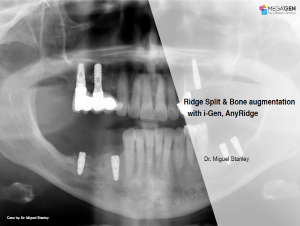

e.g. product name, treatment solution, author, clinician name